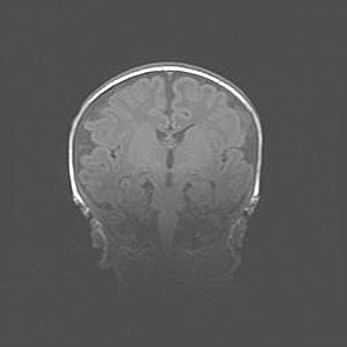

Сообщающаяся гидроцефалия. Кистозная энцефаломаляция головного мозга.

Возраст: 3 месяца 4 дня

Вес: 3100 г

Пол: женский

Окружность головы: 34 см

Срок гестации: 31 неделя

Кистозная энцефаломаляция головного мозга - одна из форм поражения головного мозга в детском возрасте. Характеризуется возникновением множественных и распространённых кист в коре, белом веществе и подкорковых образованиях головного мозга у плодов, новорождённых и детей раннего возраста. Развитие кистозной энцефаломаляции связано с внутриутробной асфиксией и гипотонией, родовой травмой, тромбозом синусов, пороками развития сосудов, инфекциями, сепсисом и другими причинами. Наиболее значимые инфекционные агенты: вирусы простого герпеса, цитомегалии, краснухи, токсоплазмы, энтеробактерии, золотистый стафилококк и другие.